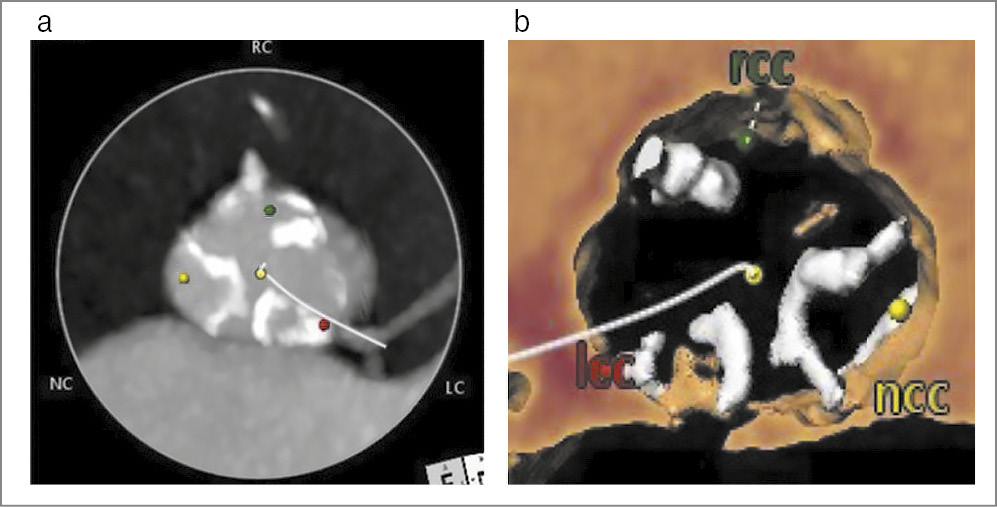

КТ: кальциноз створок и фиброзного кольца трехстворчатого аортального клапана (рис. 2).

Рис. 2. КТ (a) и 3D-реконструкция (b) аортального клапана. Виден трехстворчатый аортальный клапан с кальцинатами в основании и краях створок, характерными для лучевого поражения клапанов.